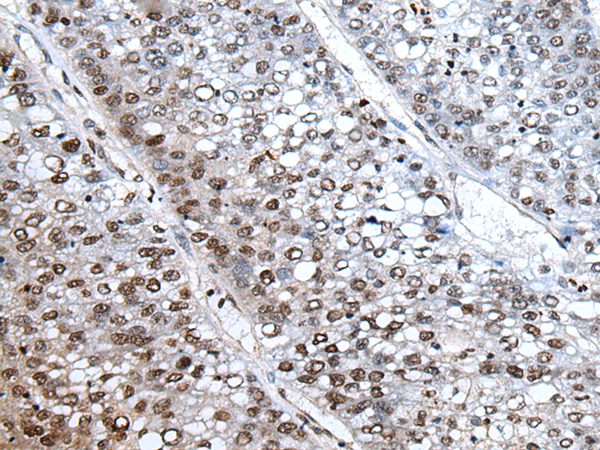

IHC positive control:

Human liver cancer

IHC Recommend dilution:

25-100